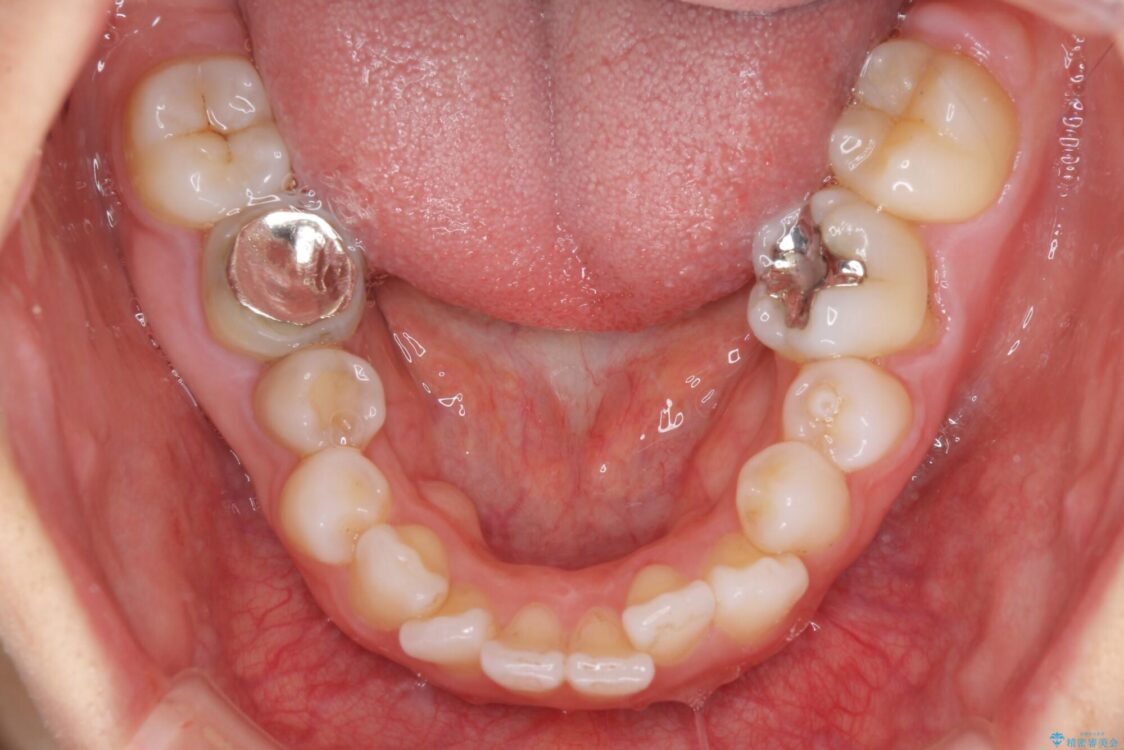

左下の大臼歯2本が顕著に舌側に傾斜しているため、まずは奥歯の咬み合わせを改善をし、その後上下左右の第1小臼歯4本を抜歯することで口元を引っ込めながら整えることとしました。

治療前

• 【モニター】出っ歯と咬み合わせを改善 ワイヤー装置の抜歯矯正 治療前画像

治療途中

• 【モニター】出っ歯と咬み合わせを改善 ワイヤー装置の抜歯矯正 治療途中画像